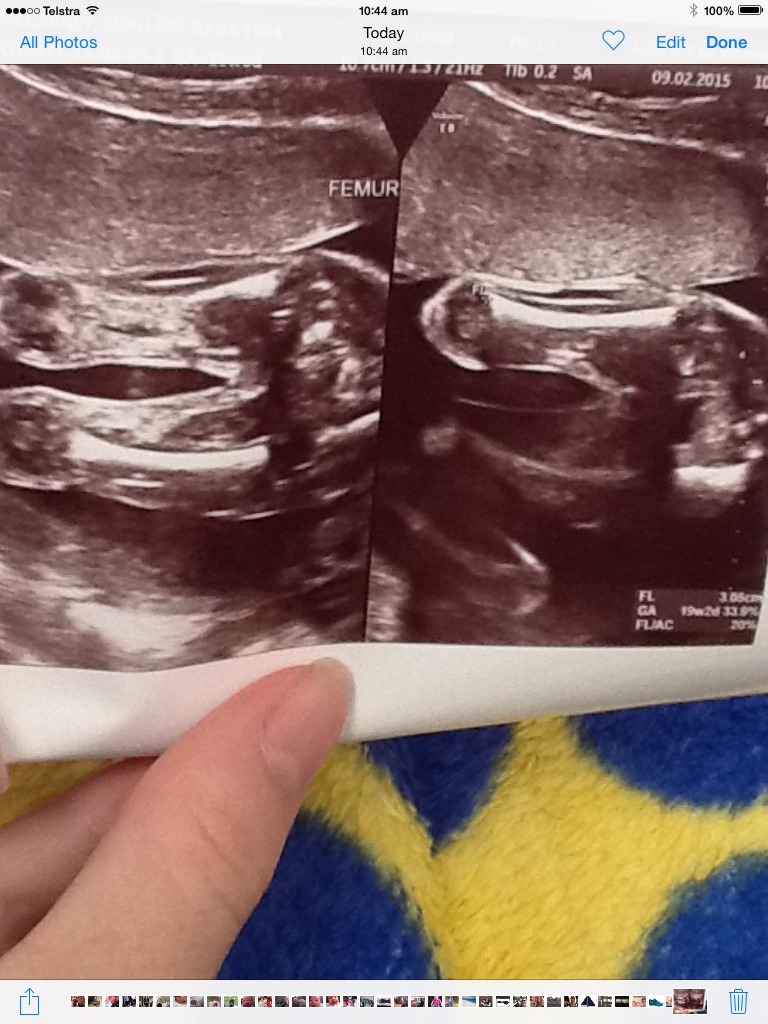

19 weeks and 2 days. What do you think?Attachment 25070

I would say girl :).

Also thinking girl but legs look a little close together.

Guessing girl, but can't really see any girl or boy parts.

Could be girl but in the first pic there looks to be something that looks like a penis. I'm split 50/50

Leaning girl but not sure.